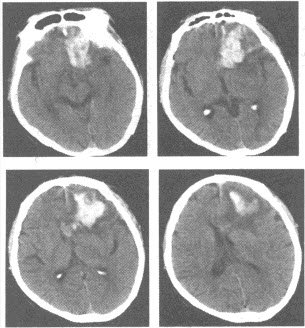

男,47岁,外伤后CT检查所见,最可能的诊断为()

A:脑膜瘤

B:脑转移瘤

C:钙化灶

D:胶质瘤

E:脑出血